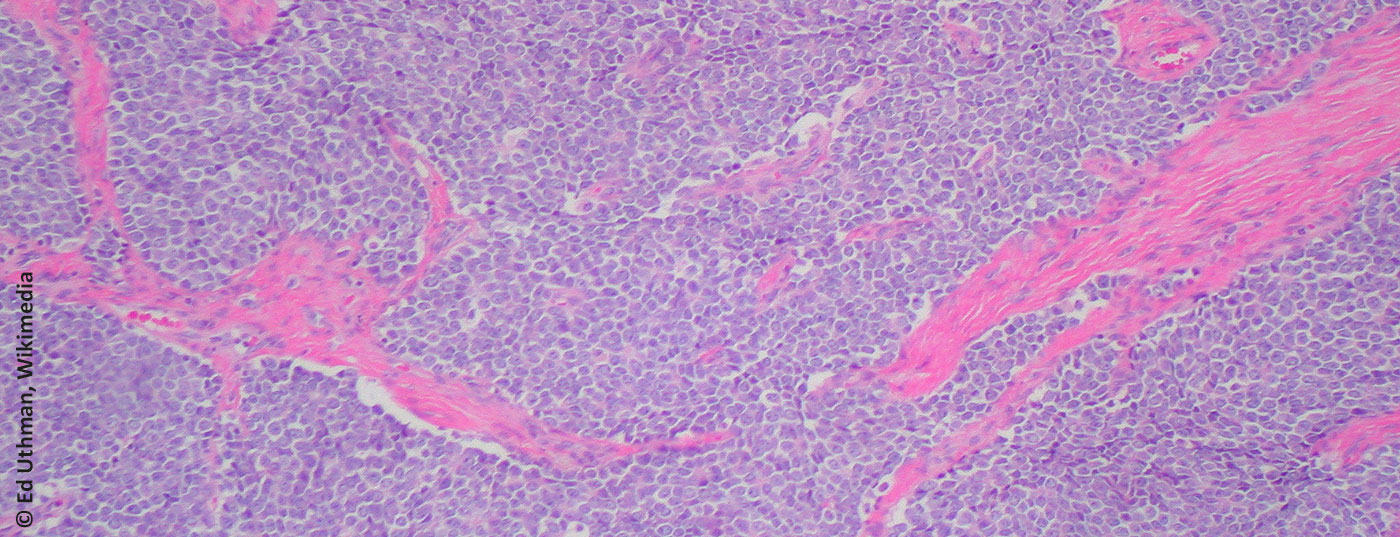

Management des zweithäufigsten primären malignen Knochentumors

Zur Therapie der Wahl beim Ewing-Sarkom gehören eine neoadjuvante Chemotherapie, eine Tumorresektion und eine postoperative Chemotherapie mit/ohne Radiotherapie. Dabei ist das interdisziplinäre Management an einem entsprechenden Zentrum von entscheidender Bedeutung.